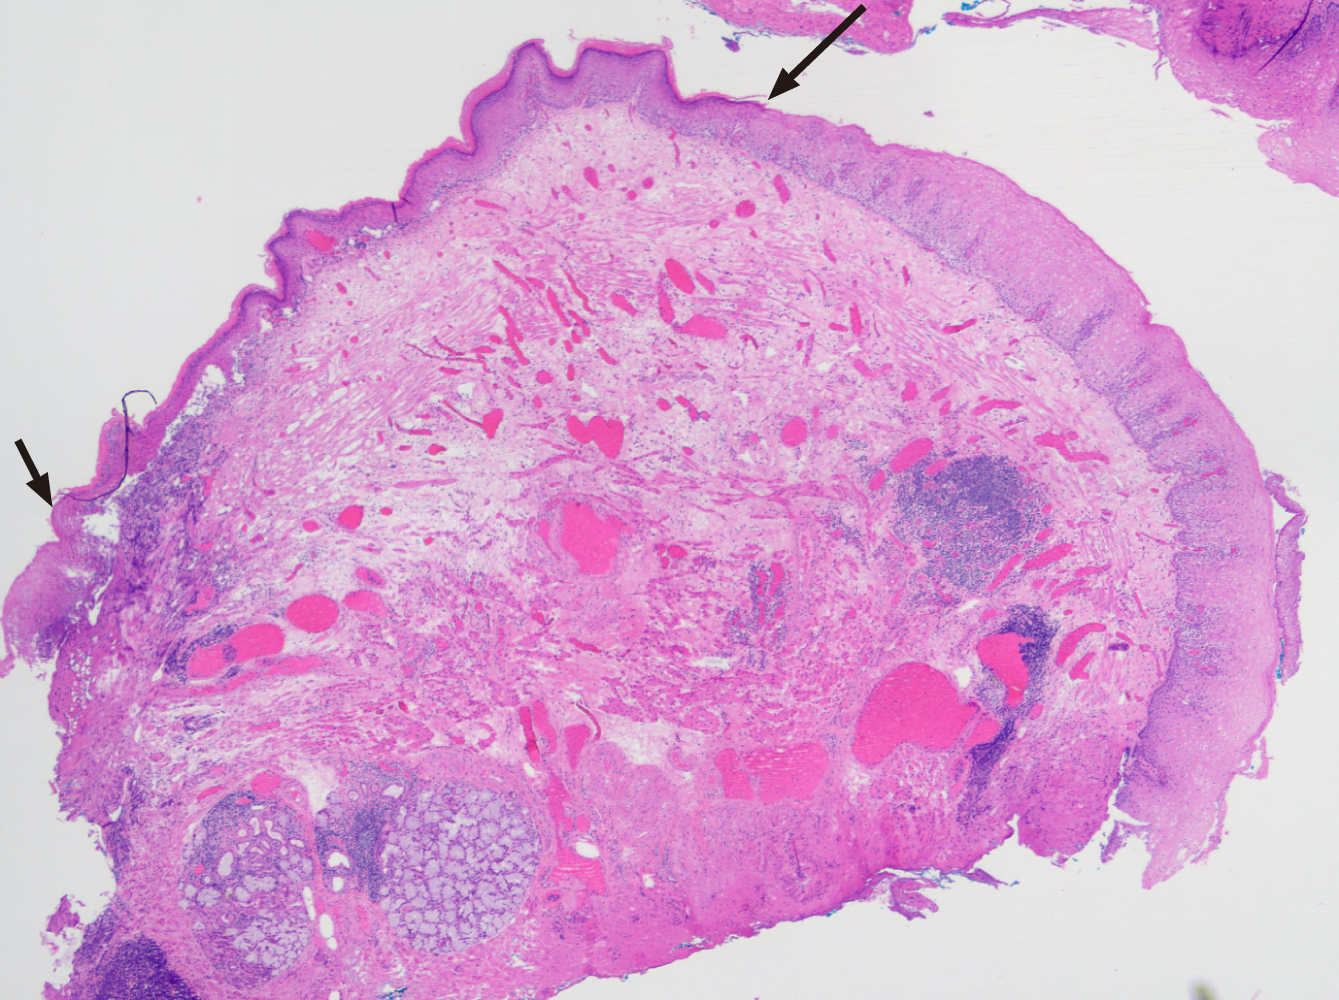

Endoscopic imaging was performed by repeat gastroscopy, which revealed a white patch about 10-15 mm in size adjacent to the stable Barrett's segment in the lower oesophagus at 39 cm (Figures 1 and 2). Biopsy revealed oesophageal squ

Endoscopically and histologically, the diagnosis was EEM.